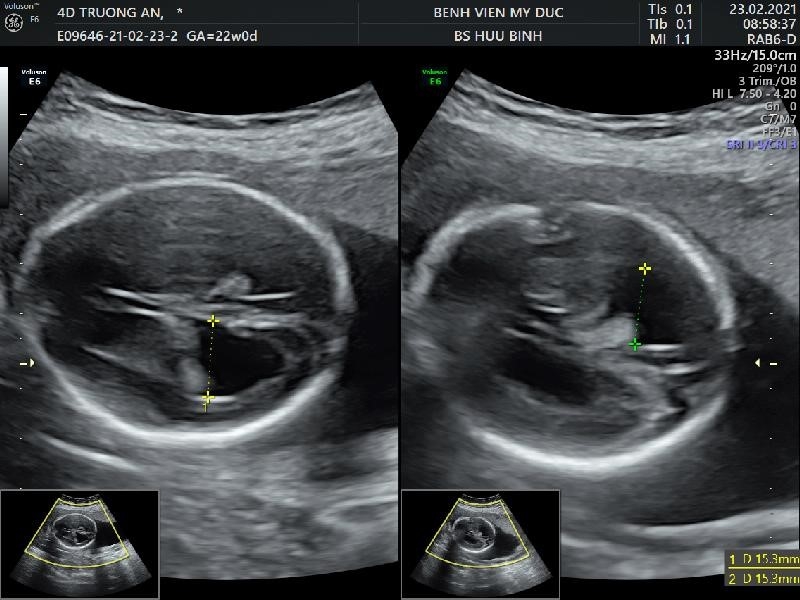

- Patient 28 years old, PARA 0000 – Natural pregnancy.

- Ultrasound at 22 weeks recorded: big tongue, 2 big kidneys, thick placenta, big baby.

Image: thick placenta, large tongue, large kidneys on ultrasound.

- Baby after birth: cesarean section at 34 17/week – weight 3100g

- The placenta weighs 2500g – Baby died 4 days after birth due to infection